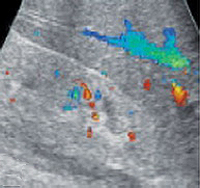

При проведении пробы Зимницкого выявляется изогипостенурия. УЗИ почек свидетельствует о снижении толщины паренхимы и уменьшении размера почек. Снижение внутриорганного и магистрального почечного кровотока выявляется на УЗДГ сосудов почек. Рентгенконтрастную урографию следует применять с осторожностью из-за нефротоксичности многих контрастных препаратов. Перечень других диагностических процедур определяется характером патологии, ставшей причиной развития ХПН.

При проведении пробы Зимницкого выявляется изогипостенурия. УЗИ почек свидетельствует о снижении толщины паренхимы и уменьшении размера почек. Снижение внутриорганного и магистрального почечного кровотока выявляется на УЗДГ сосудов почек. Рентгенконтрастную урографию следует применять с осторожностью из-за нефротоксичности многих контрастных препаратов.